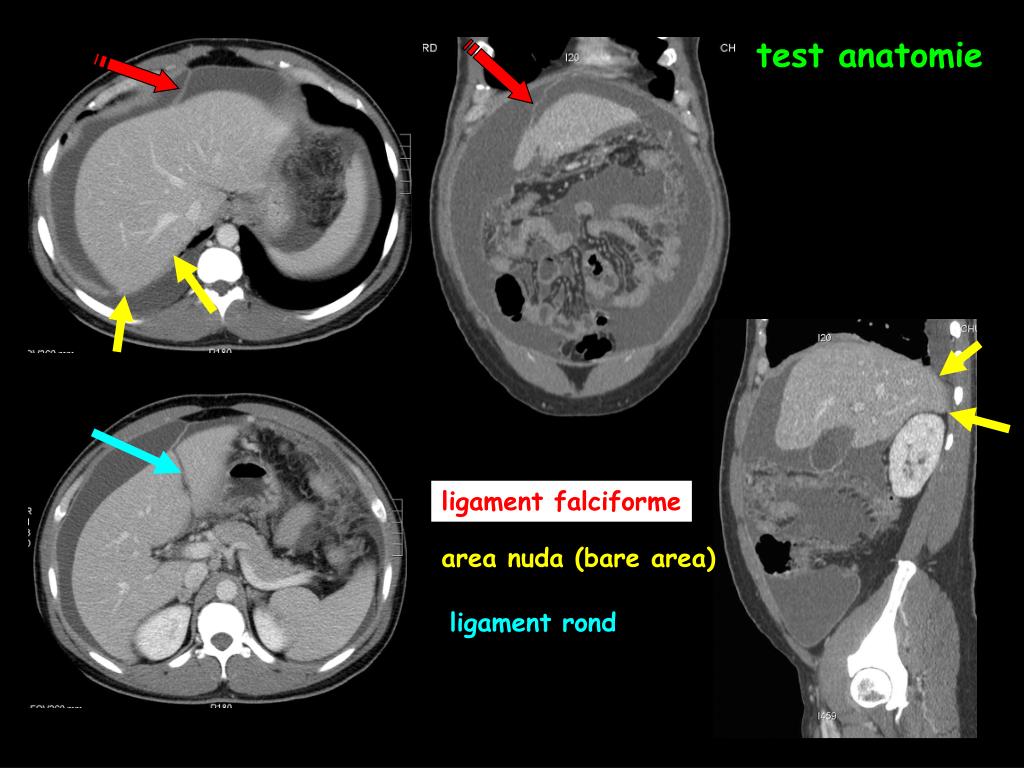

17. poche de Morison cul de sac de Douglas et récessus latéro rectaux les éléments anatomiques et les données physiologiques ( variations de pression liées à la respiration et localisation dans les zones "déclives" des collections liquidiennes ) expliquent les "points chauds" à surveiller dans la cavité péritonéale

25. test anatomie test ligament falciforme area nuda (bare area) ligament rond